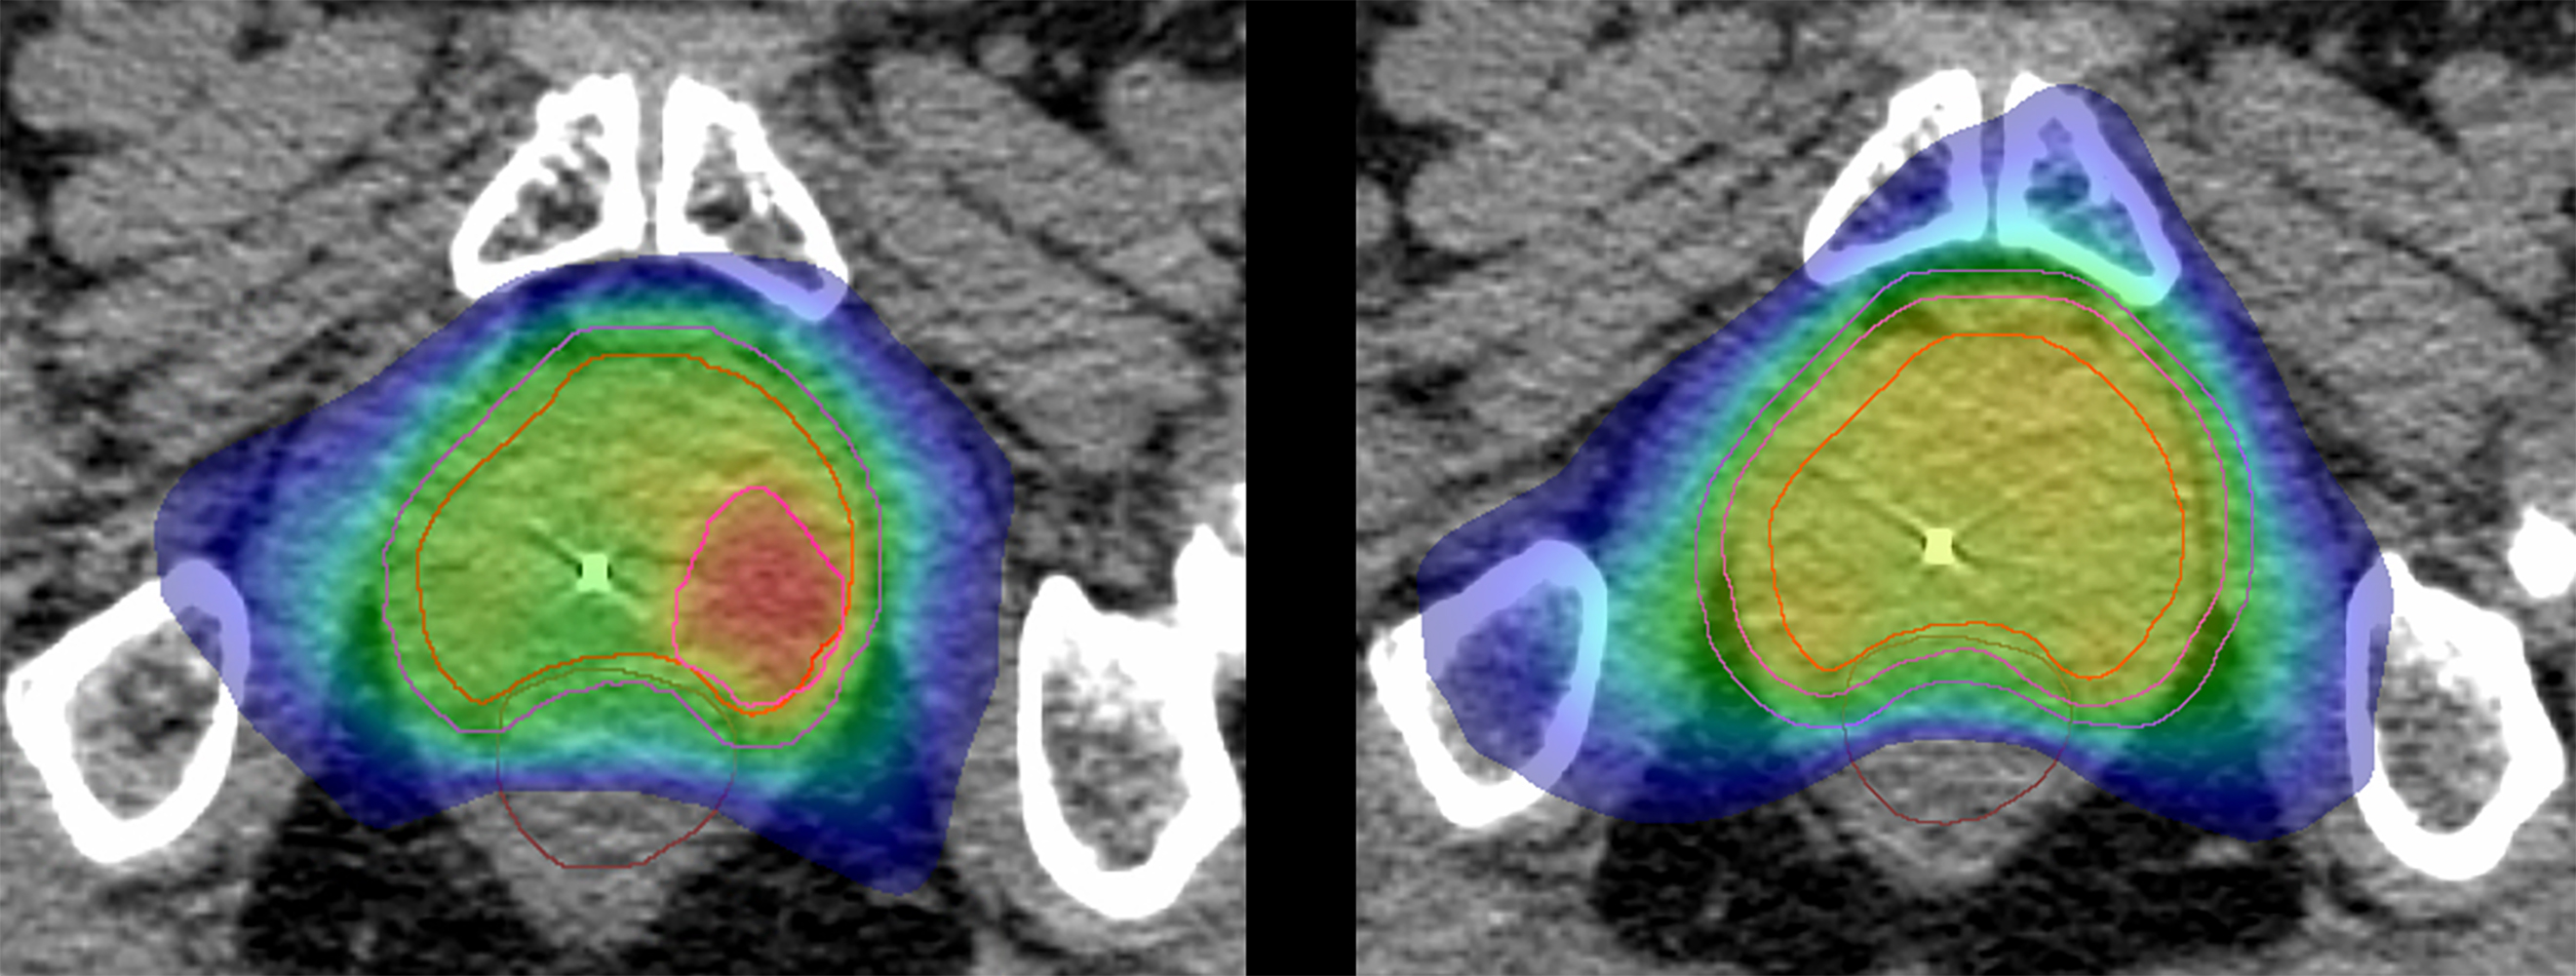

Statt wie bisher die gesamte Prostata gleichmäßig zu bestrahlen, werden im Rahmen der HypoFocal-SBRT-Studie zusätzlich gezielt jene Bereiche des Organs, in denen die hochpräzise Bildgebung den Tumor anzeigt, mit besonderer Intensität bestrahlt. Dadurch soll eine verbesserte, effektivere Therapie und Schonung des umliegenden Gewebes, wie Blase und Darm erreicht werden. Zudem verkürzt sich die Behandlungszeit deutlich.

Das Studienteam um Grosu und Junior-Co-Studienleiter Dr. Simon Spohn,Arzt an der Klinik für Strahlenheilkundedes Universitätsklinikums Freiburg,rechnet bei dem neuen Vorgehen mit einer hohen Erfolgsquote, geringen Nebenwirkungen und einer Verbesserung der Lebensqualität. „Die neue Methode verspricht eine bessere Heilungsrate bei Prostatakrebs ohne vermehrte Nebenwirkungen“, sagt PD Dr. Constantinos Zamboglou, auch Co-Projektleiter der HypoFocal-SBRT Studie. „Zusätzlich hat unsere Studie das Potenzial, die Behandlungszeit von acht auf vier Wochen oder sogar auf nur fünf Tage zu verkürzen“, ergänzt Zamboglou. Die Behandlung ist nicht invasiv und daher weniger belastend für Betroffene. Sie wird perkutan, also über die unverletzte Haut durchgeführt. Patienten benötigen weder Schmerzmittel noch eine Narkose.